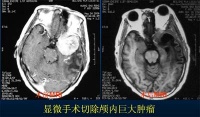

Cushing 于1903 年最早采用手术治疗高血压脑出血,由于效果极差,一度冷却下来。在过去相当长一段时期内,对脑出血多主张进行内科治疗,较少采取手术治疗。近年来,由于 CT 检查的应用,对脑出血手术病例进行合理选择,术中应用显微技术清除血肿和双极电凝止血,从而使手术更加精细准确,将损伤减少至最低程度。并采取了早期手术,即发病后24 至48 小时内手术。甚至提出超早期手术,在脑出血后7 小时内进行手术治疗。由于尽早清除血肿,降低颅内压,不仅能达到救命目的,而且有利于促进脑功能恢复,减轻残废,有人总结近5 年文献报告的929 例高血压脑出血手术治疗结果,手术死亡率为2-28%,功能恢复率达63-89%。近来在脑出血的治疗中又采用了一些新的治疗方法。如施行颅骨钻孔向血肿腔内注入尿激酶以促进血块液化,然后予以抽吸。此法简便易行,疗效肯定。另外还开展了cT 导向脑立体定向清除血肿及CT 定位,应用内窥镜进行血肿清除等方法。这些治疗方式不仅损伤小,且疗效亦好,病人乐于接受。随着新的诊疗方法不断涌现,高血压脑出血的治疗效果将不断获得改善。